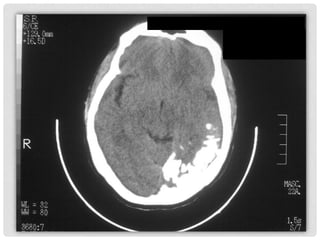

TOMOGRAFIA

COMPUTADA

DE CRANEO

TC

Se corroboran las calcificaciones

intracraneanas, extensas,

unilaterales, con patrón giriforme

en topografía del hemisferio

cerebral izquierdo, de predominio

posterior, en el lóbulo temporal.